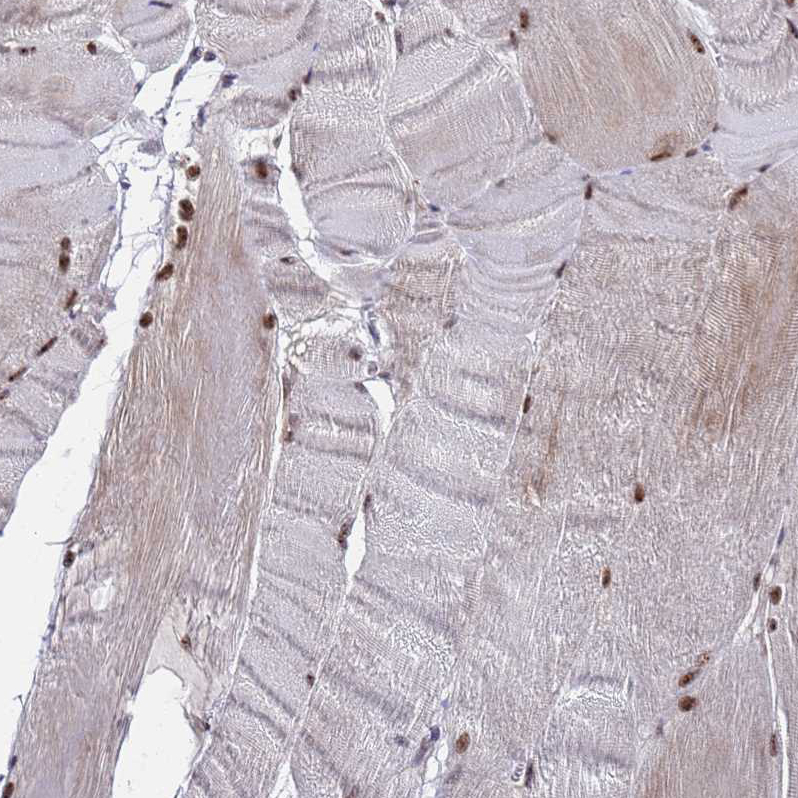

Immunohistochemical staining of human skeletal muscle shows strong nuclear positivity in myocytes.